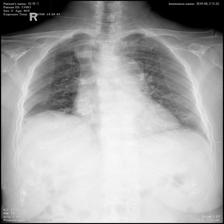

To pre-train a high-performance X-ray foundation model, the first thing we need to do is the collection of large-scale X-ray images. Therefore, a large-scale and high-resolution dataset that contains X-ray medical images is collected for the pre-training. Some representative samples are visualized in Fig. 3.